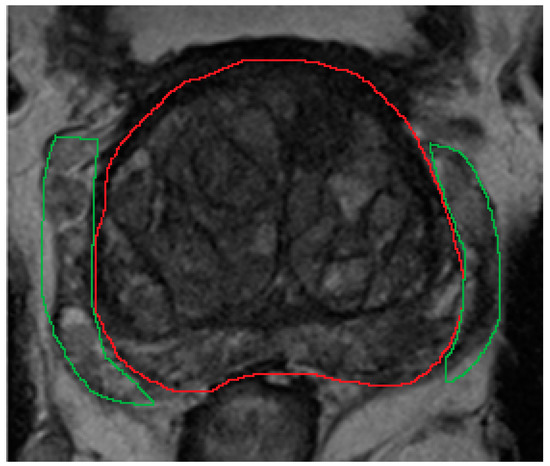

2.2. Segmentation

2.2.3. Zonal Segmentation